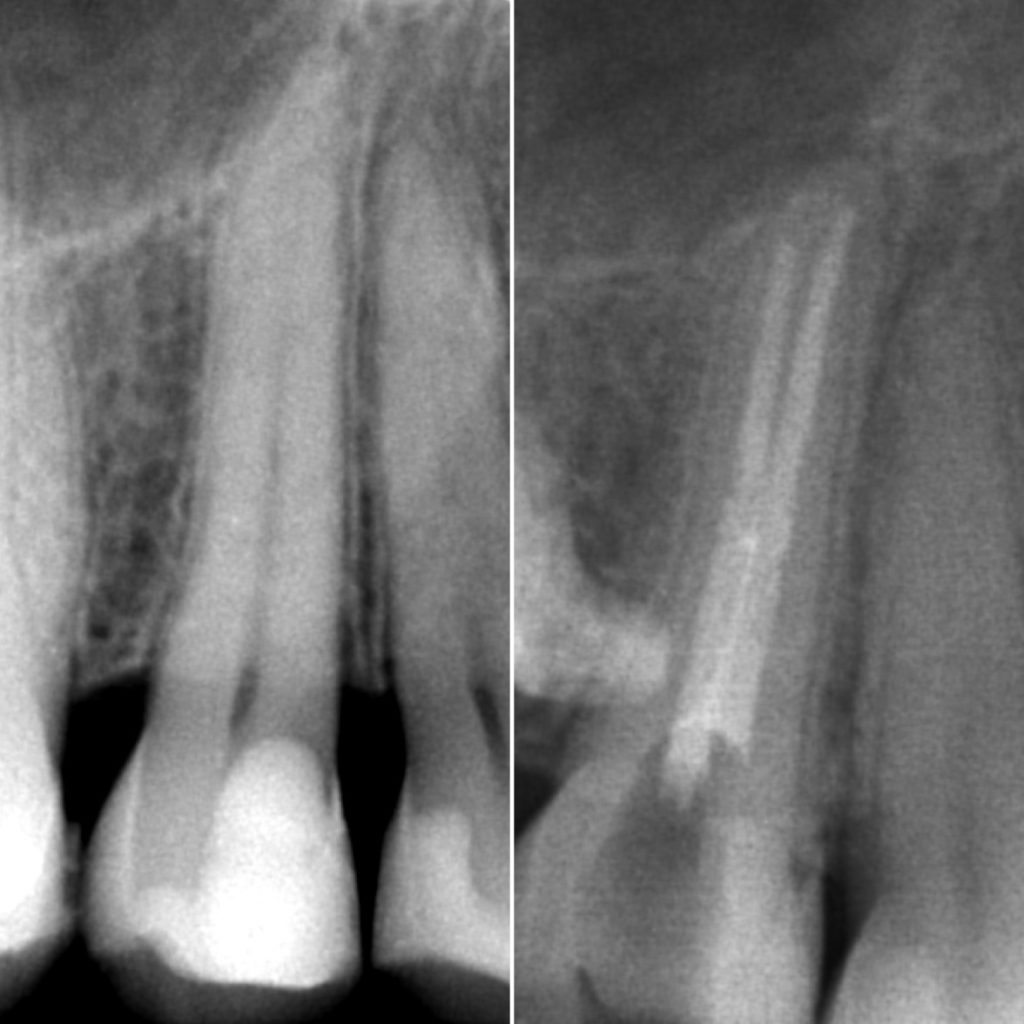

• Диагностика и лечение кариеса и его осложнений (пульпиты, периодонтиты)

• Эндодонтическое лечение корневых каналов с использованием стоматологического микроскопа